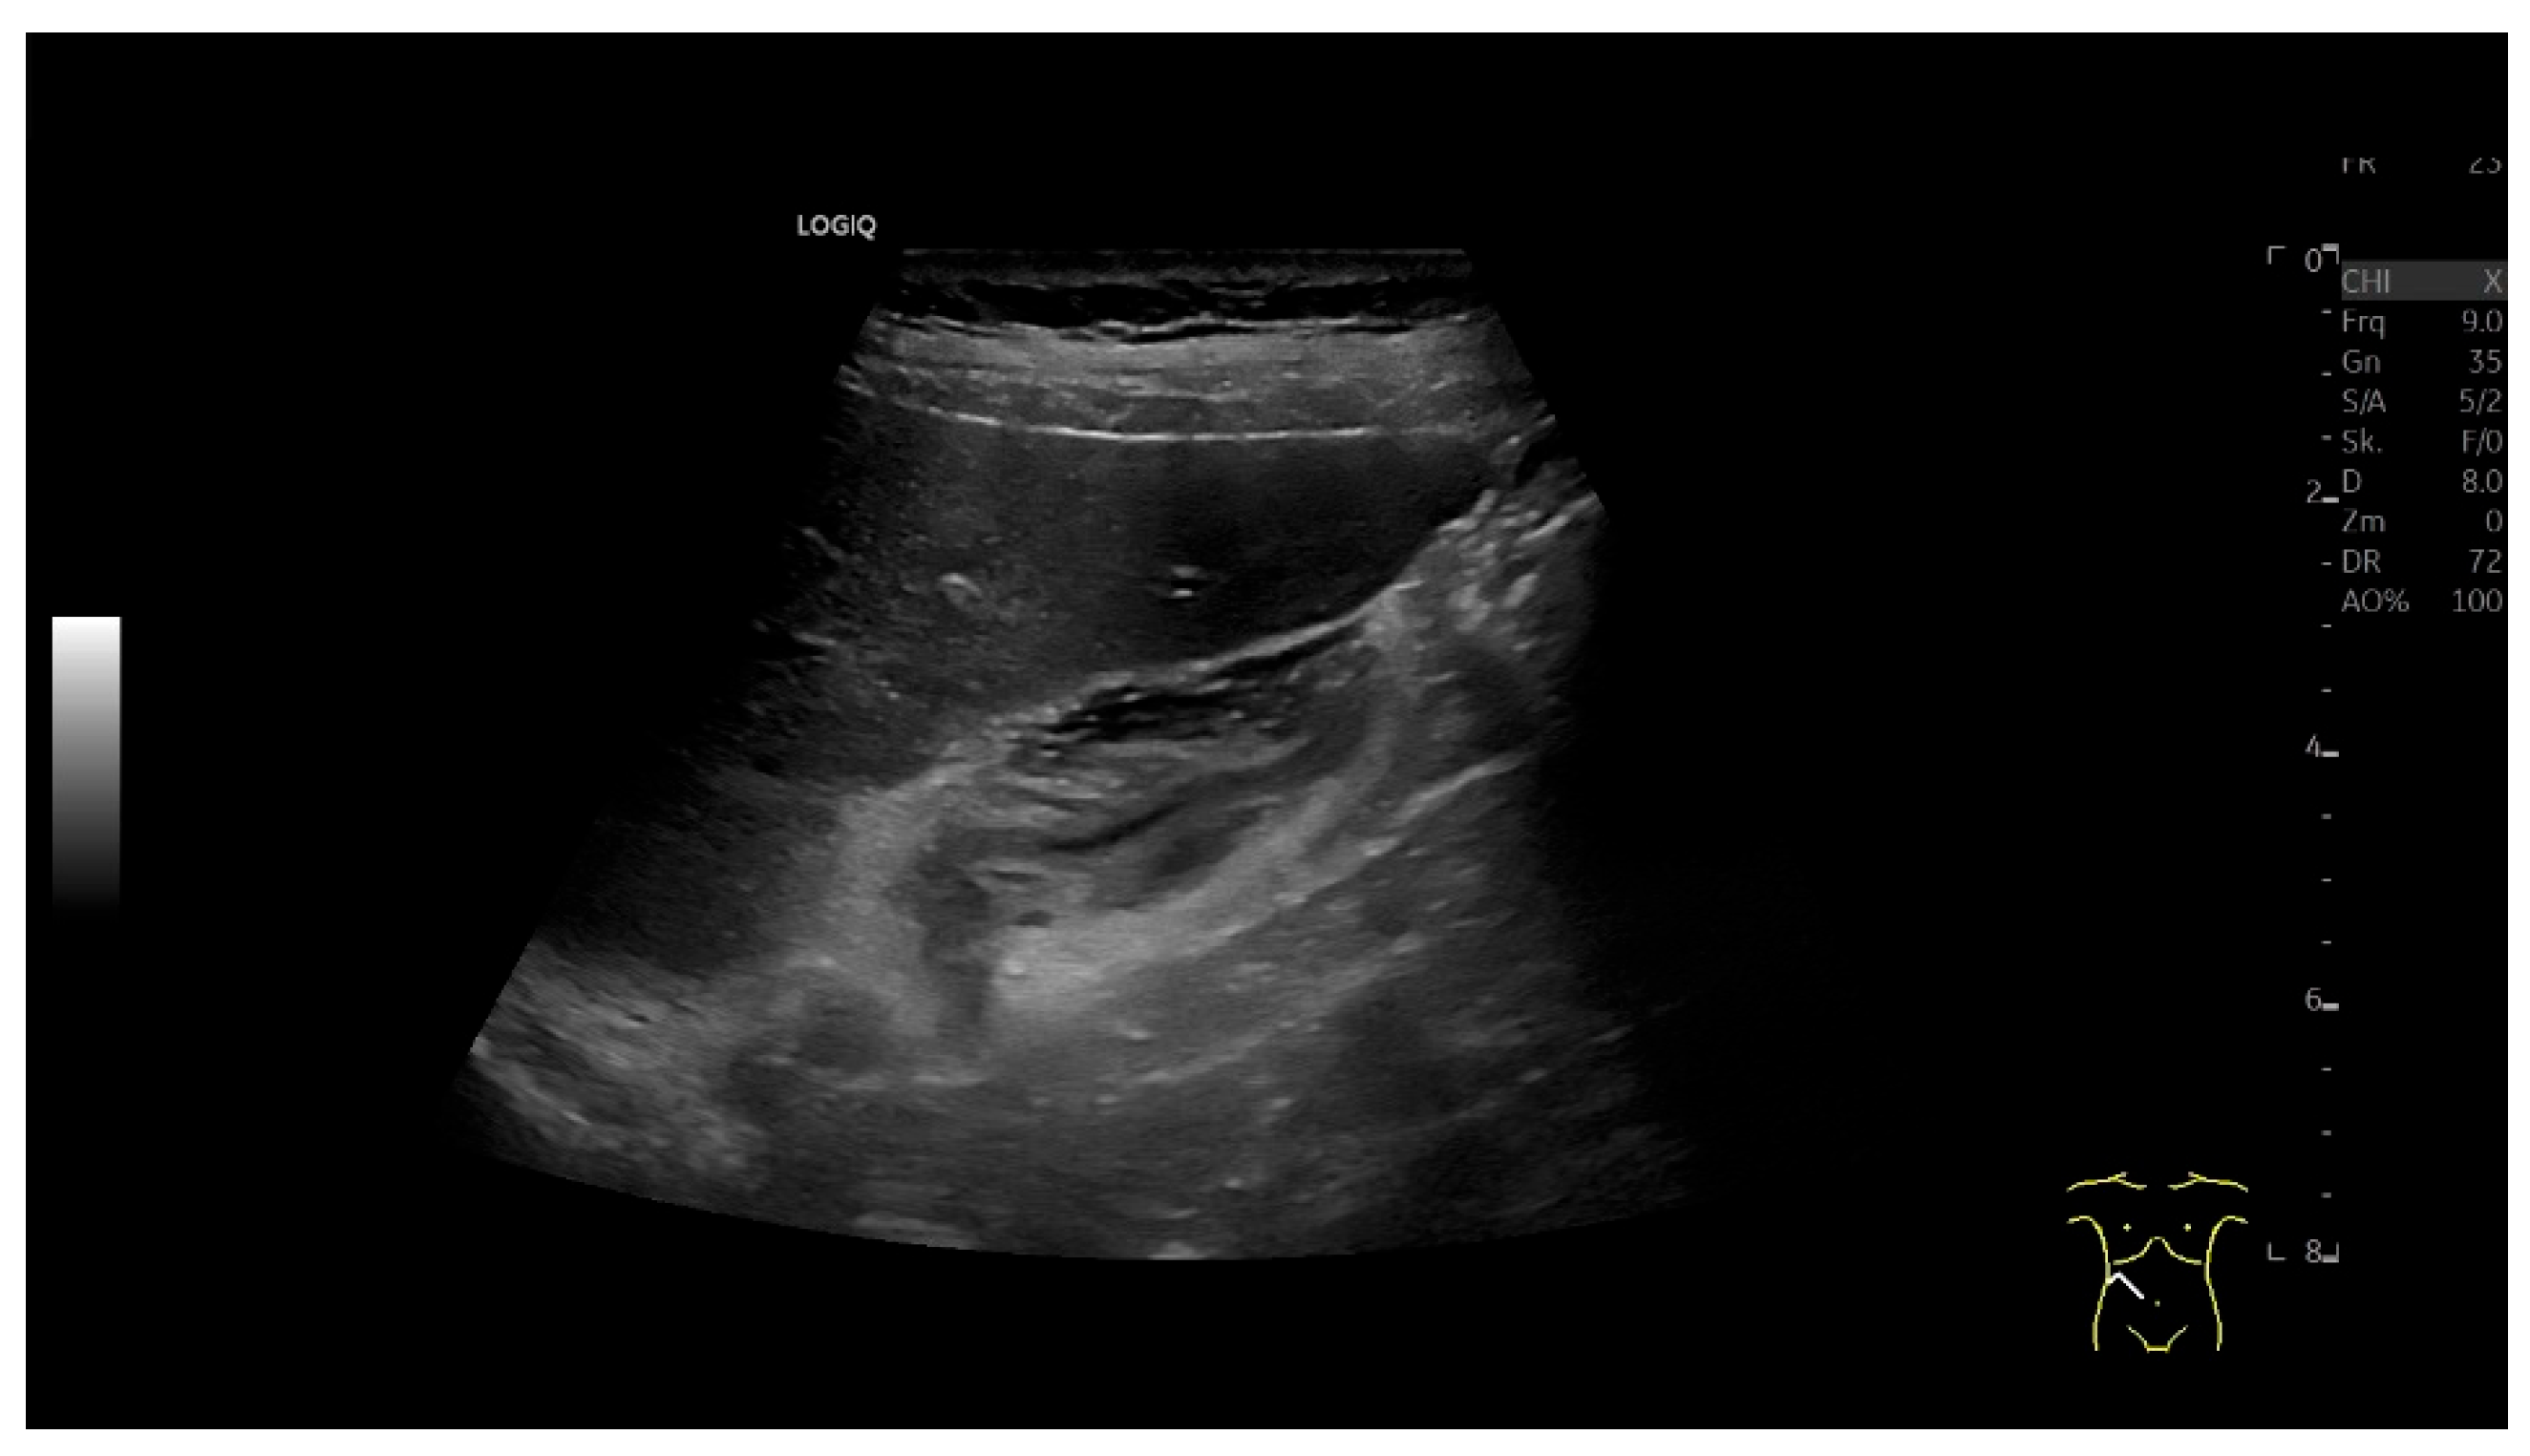

4.4. Gallstones